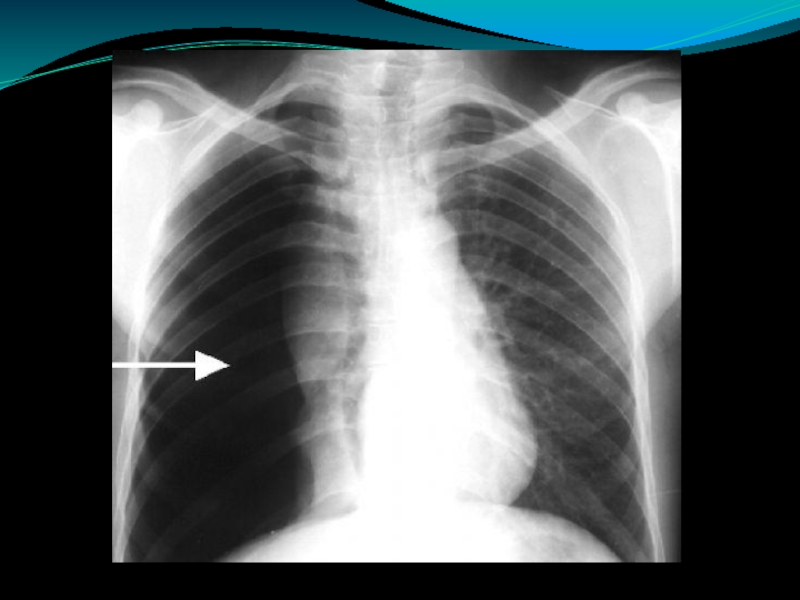

Слайд 5Окончательное подтверждение диагноза происходит после проведения рентгенологического исследования.

Коллабированное лёгкое

Отсутствие лёгочного рисунка

Смещение

тени средостения в противоположную сторону от коллапса